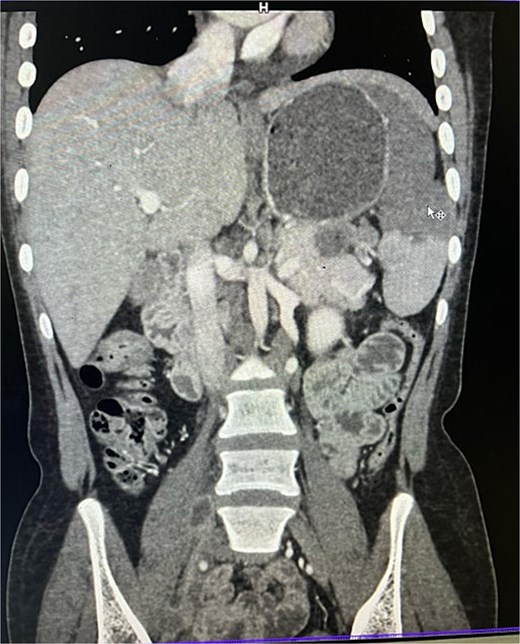

On imaging, ultrasonography showed a lobulated hypoechoic lesion in the region of the pancreatic tail and splenic hilum. This was very not conclusive, so a contrast-enhanced CT scan was planned, which revealed multiple necrotic, conglomerated lymph nodes (30 × 33 × 38 mm) near the splenic hilum and pancreatic tail, abutting the stomach and spleen, with maintained fat planes (Fig. 1). A splenic infarct involving a significant portion of the parenchyma was noted (Fig. 2), with multiple additional necrotic nodes along the retroperitoneum (paraaortic and iliac vessels) and mild pelvic free fluid. Then, CT-guided biopsy from the lymph nodal mass was planned, which showed moderately cellular smears showed caseous necrotic debris, lymphocytes, and clusters of epithelioid cells, suggestive of chronic necrotizing lesion consistent with TB.

Contrast enhanced computer tomography (CECT) abdomen showing necrotic lymph node mass near pancreatic tail and splenic hilum.

CECT abdomen showing splenic infarct involving significant portion of splenic parenchyma—except at the lower pole of spleen.